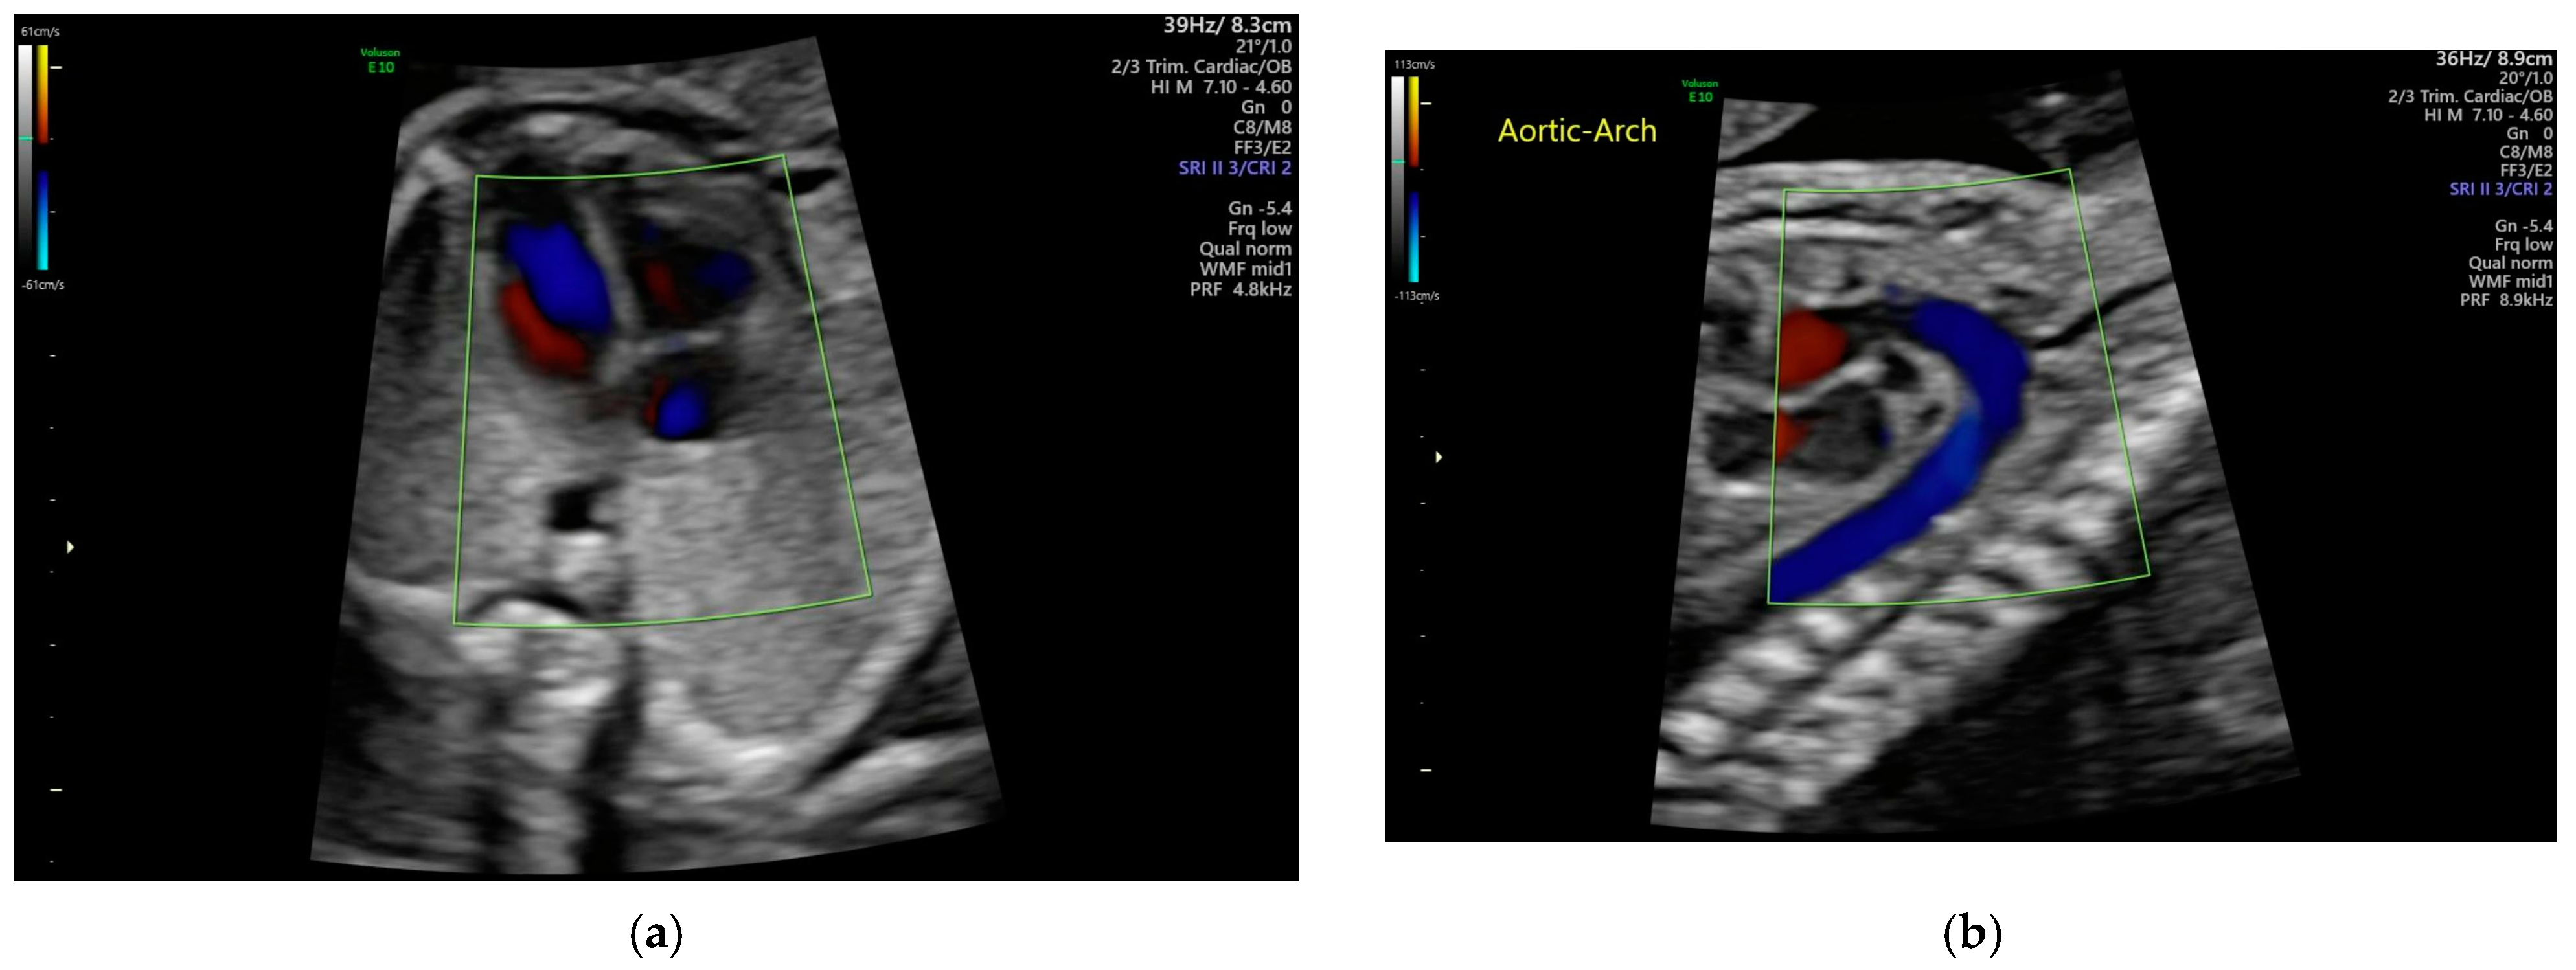

2.1. Techniques of AI

4.6. One Case Study [57]